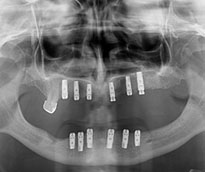

Ýmplant

Protezler